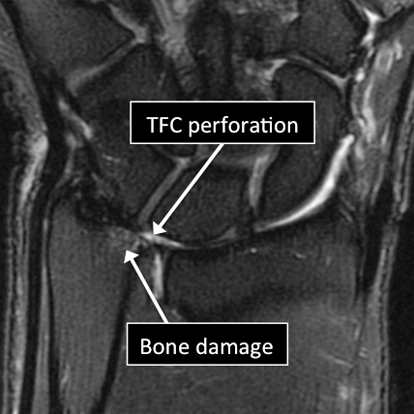

- Common things include fractures (broken bone), ligament and tendon tears, damage to the Triangular Fibrocartilage of the wrist (perforations and degeneration), osteoarthritis, tumors, among others.

Wrist MRI examinations showing normal (top) and abnormal (bottom) TFC.

Why Translational MRI of the wrist?

- In the wrist, as in many other parts of the body there are certain structures that can’t be seen (they look black or dark) with the standard MRI.

- There are new “software” programs that allow us to see structures with different contrast (bright versus dark).

- Some of these “invisible” or dark structures are unique to the wrist (Triangular Fibrocartilage or TFC) and others are found in other parts of the body (e.g. cartilage, tendons, ligaments, cortical bone).